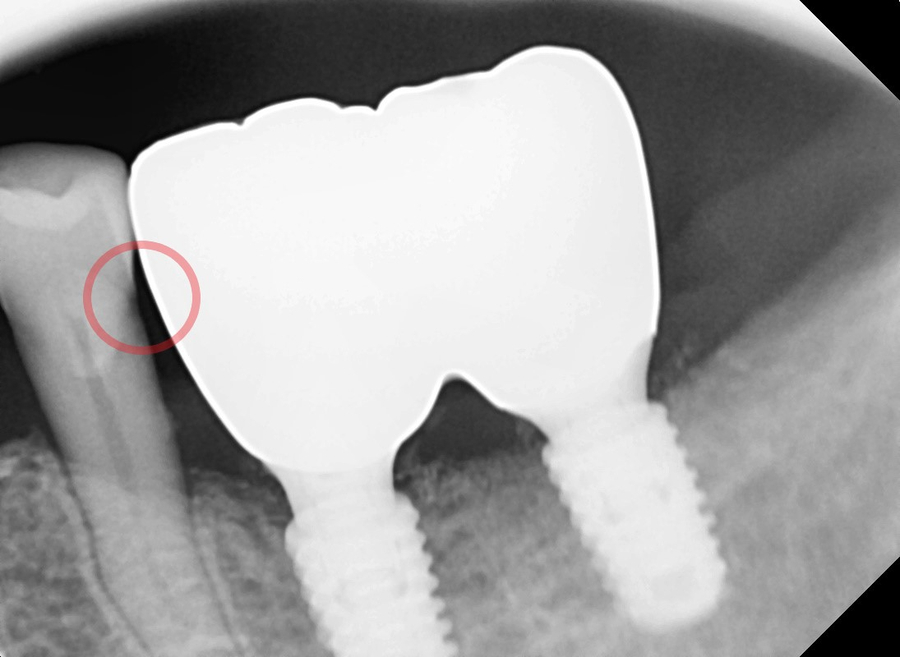

엑스레이 사진을 통해

임플란트에 문제가 없는지 확인하려는 찰나,

230926 치아 사이 충치

임플란트와 바로 옆 자연치아 틈새에 약간의 충치가

진행되고 있는 걸 발견했습니다.

충치가 심하지 않아

지금 바로 치료하기에는 아까워서,

환자분께 치간칫솔로 관리 잘해주시고

다음 번 정기검진일에 꼭 내원해달라고 말씀드렸던 기억이 납니다.

1년 반이라는 시간이 꽤 길었던 건지

이미 충치가 많이 커진 상태였어요.

1년 반 전 엑스레이 사진과 그 후 사진입니다.

충치 크기 차이가 꽤 많이 나죠?